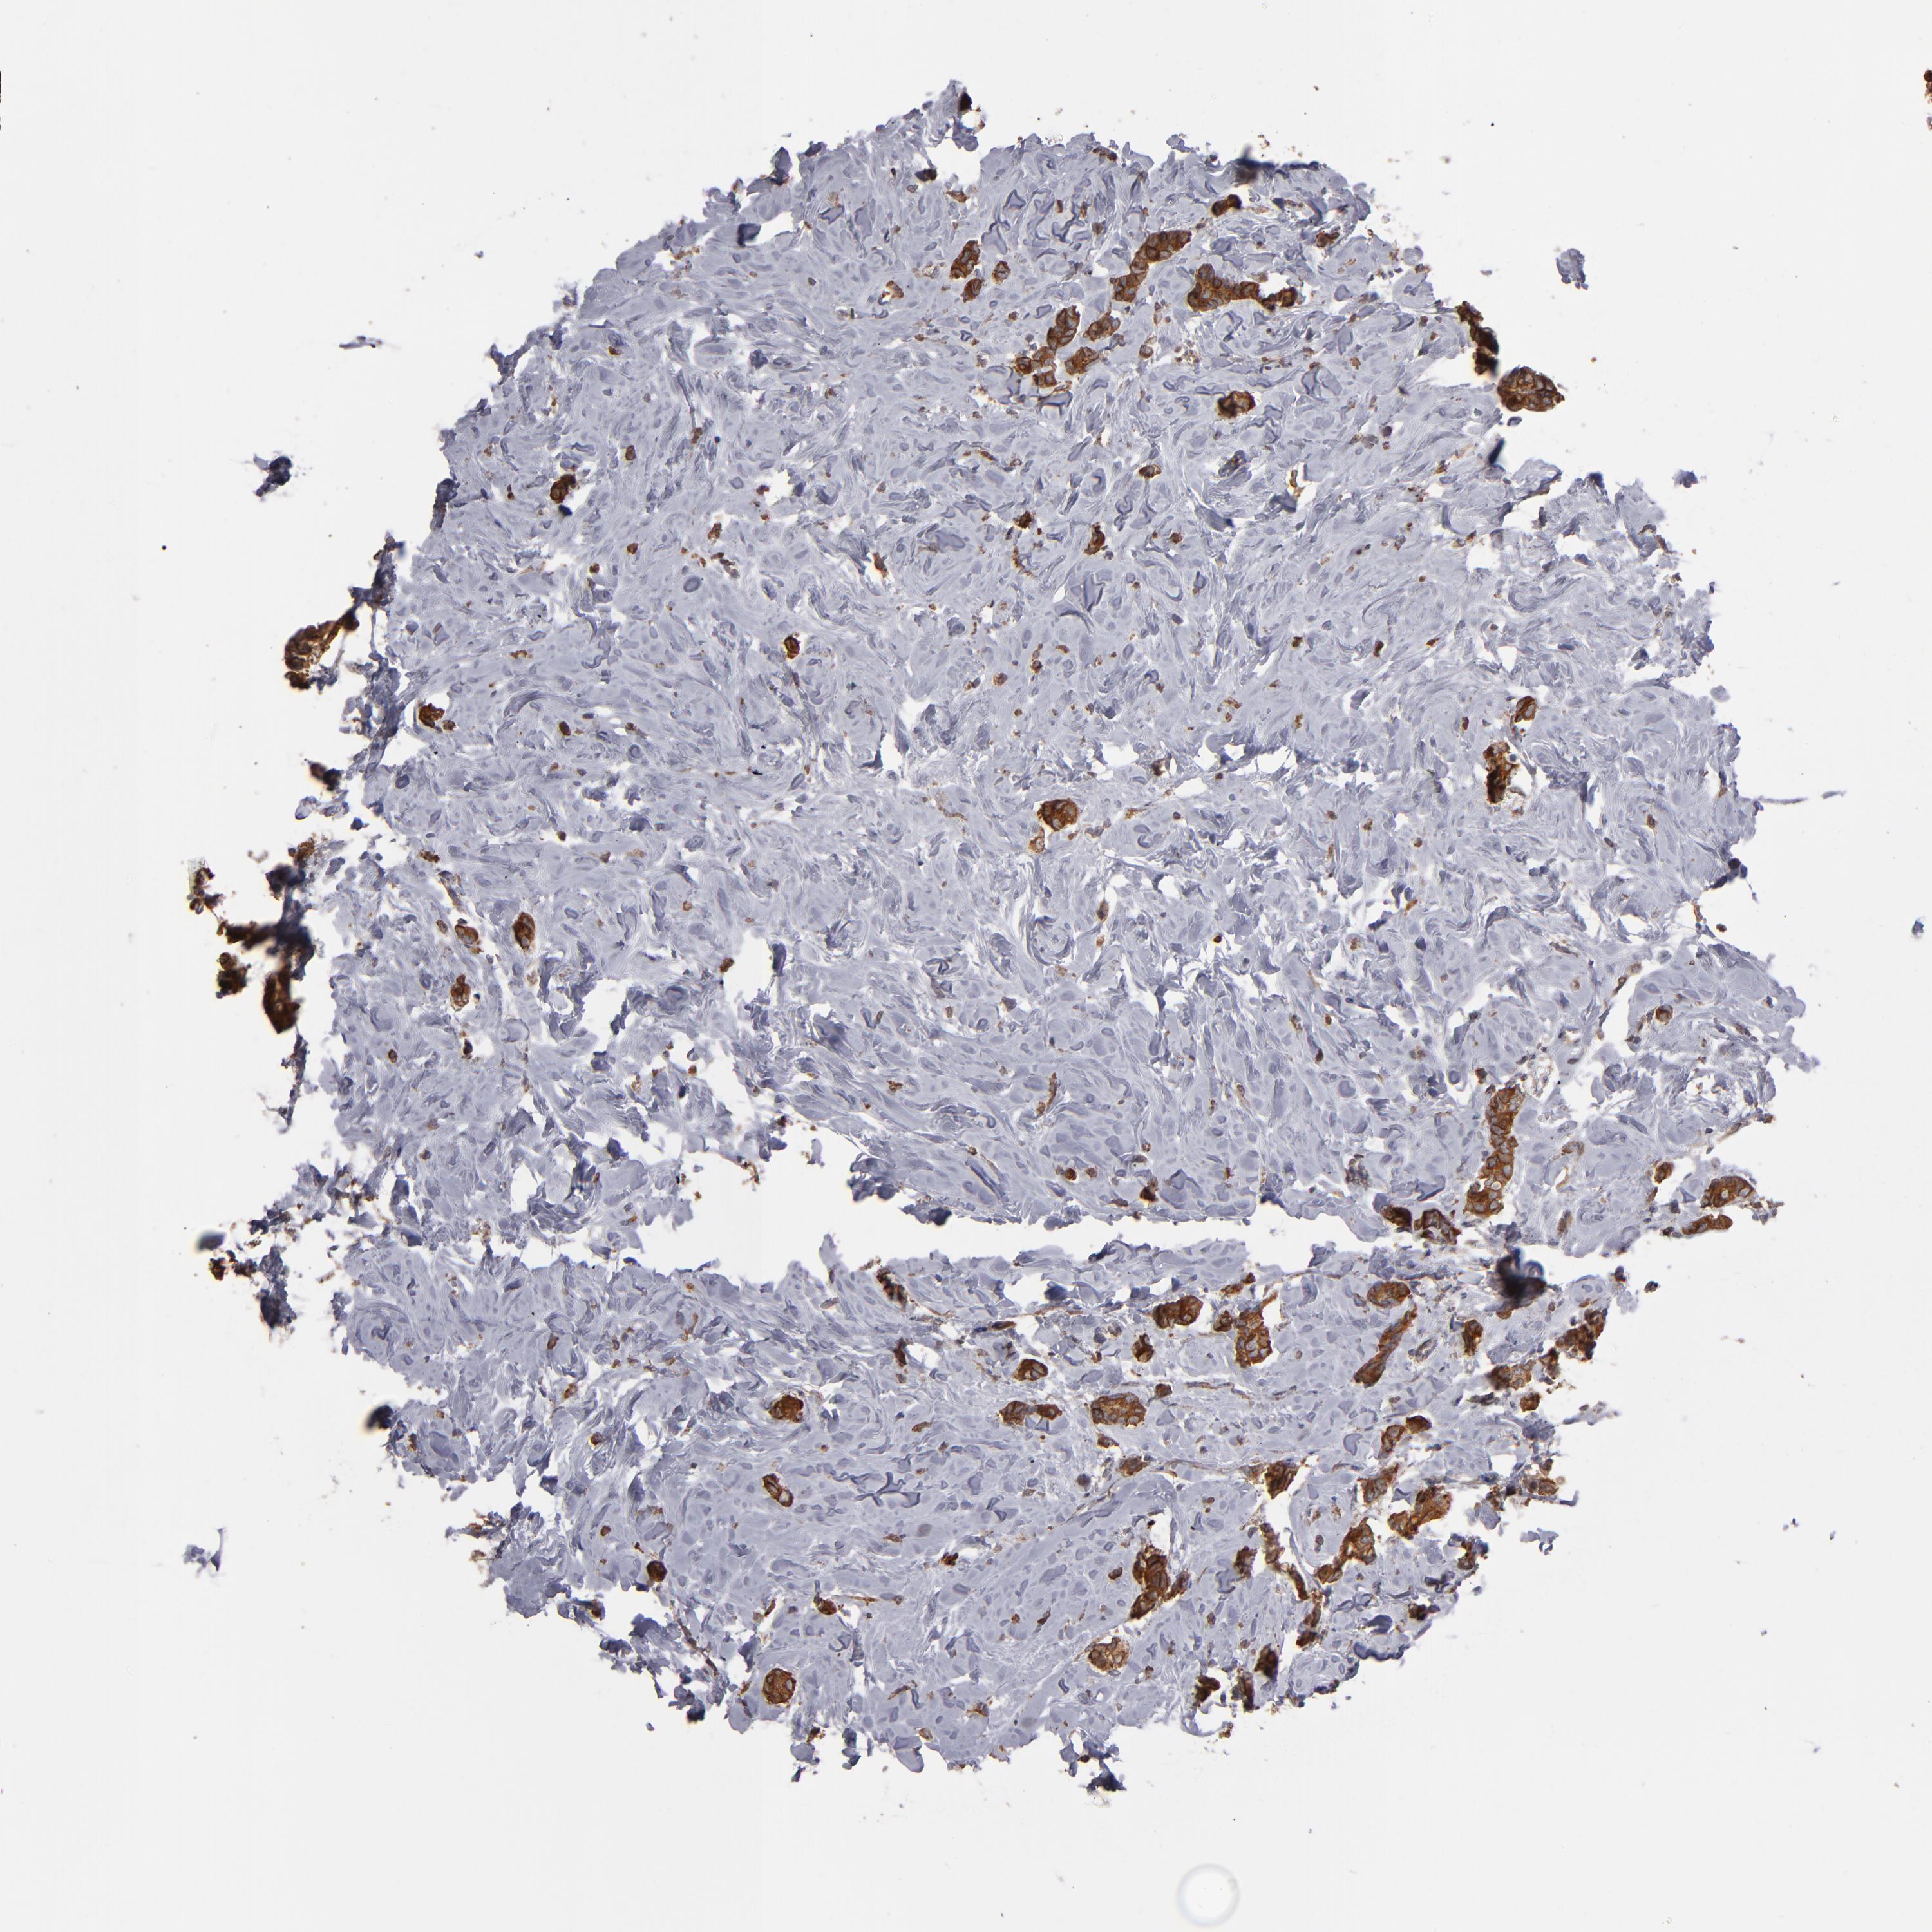

CANCER BREAST CANCER Show tissue menu

BRCA TCGA BRCA VALIDATION PROTEIN EXPRESSION